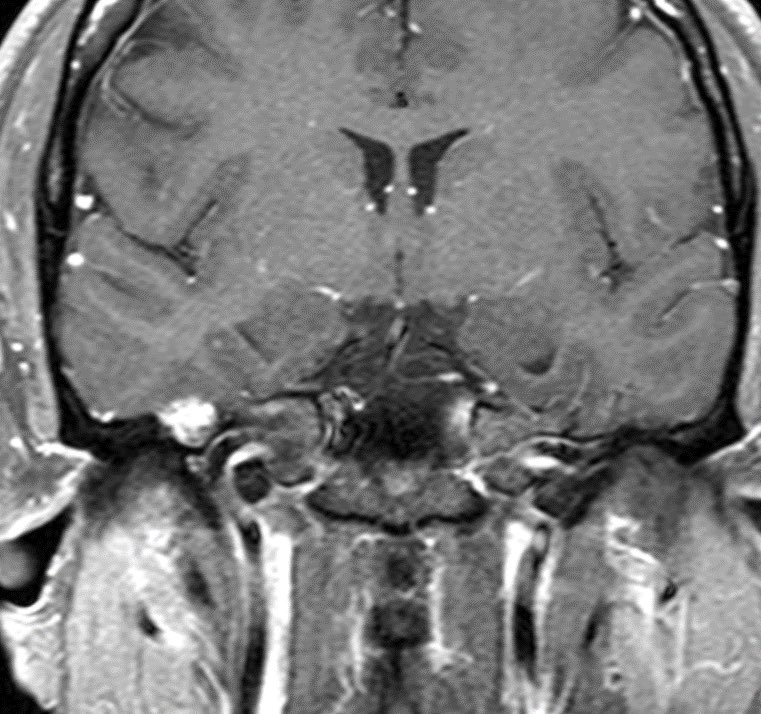

⭐️ Answer: Cortical vein thrombosis (CVT)